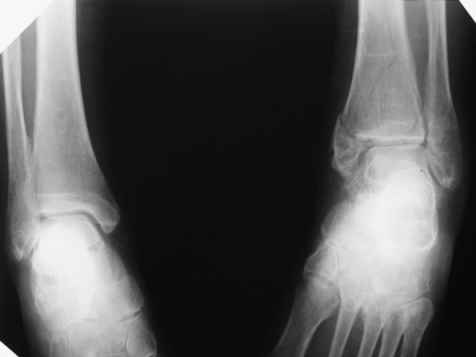

Посмотрели снимки после репозиции - не понравилась зона синдесмоза.

Сделали 3/4-е - впечатление, что в 99-том там что-то было. На

5.11.09г. запланирована КТ.

1. С учетом анамнеза и развалившегося метаэпифиза, можно-ли

надеяться на консолидацию если оставить все "как есть"?

2. Если "нет", то каков рациональный объем хирургической агрессии?

3. Следует-ли считать правомерным следующее предположение:

"Отказавшись от операции сейчас, под давлением аргументов об

удовлетворительном стоянии отломков, мы упускаем время для

остеосинтеза, а через три месяца, констатировав несращение,

вынуждены будем планировать артродез в гораздо менее благоприятных

условиях."